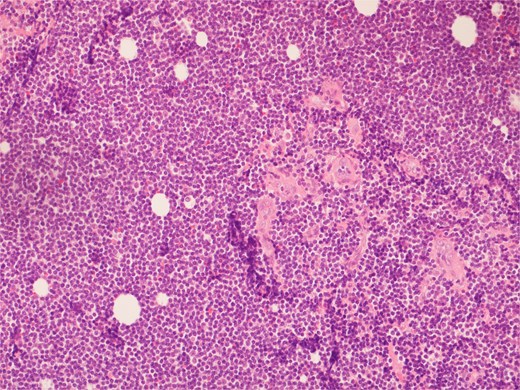

Histopathological examination of surgical specimens revealed three distinct neoplasms: (i) invasive colonic adenocarcinoma (Figs 4 and 5), (ii) jejunal NET (Figs 6 and 7), and (iii) small-lymphocytic lymphoma (Figs 8 and 9). Morphological assessment supported by immunohistochemical profiling confirmed each represented an independent primary, with no evidence of a shared clonal origin. The findings were subsequently reviewed at the Multidisciplinary Meeting alongside Oncology and Haematology specialists, and adjuvant single-agent chemotherapy was initiated, with planned surveillance of the indolent lymphoma.

High power view showing a proliferation of monotonous small lymphoid cells.

Diffusely and strongly positive CD20 staining of neoplastic lymphoid cells.